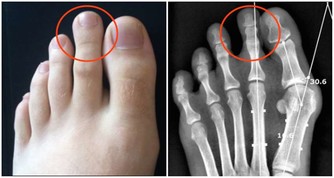

「W型坐姿」導致孩子形成內八

這種坐姿影響跳躍、投擲和踢腿等動作。當小孩以「W型坐姿」坐在地上時,膝蓋是向外翻,這種姿勢會導致孩子的髖外展肌、股後肌群、內轉肌和跟腱承受更大的壓力,還會影響孩子背部及盆骨的發育,導致孩子形成內八。